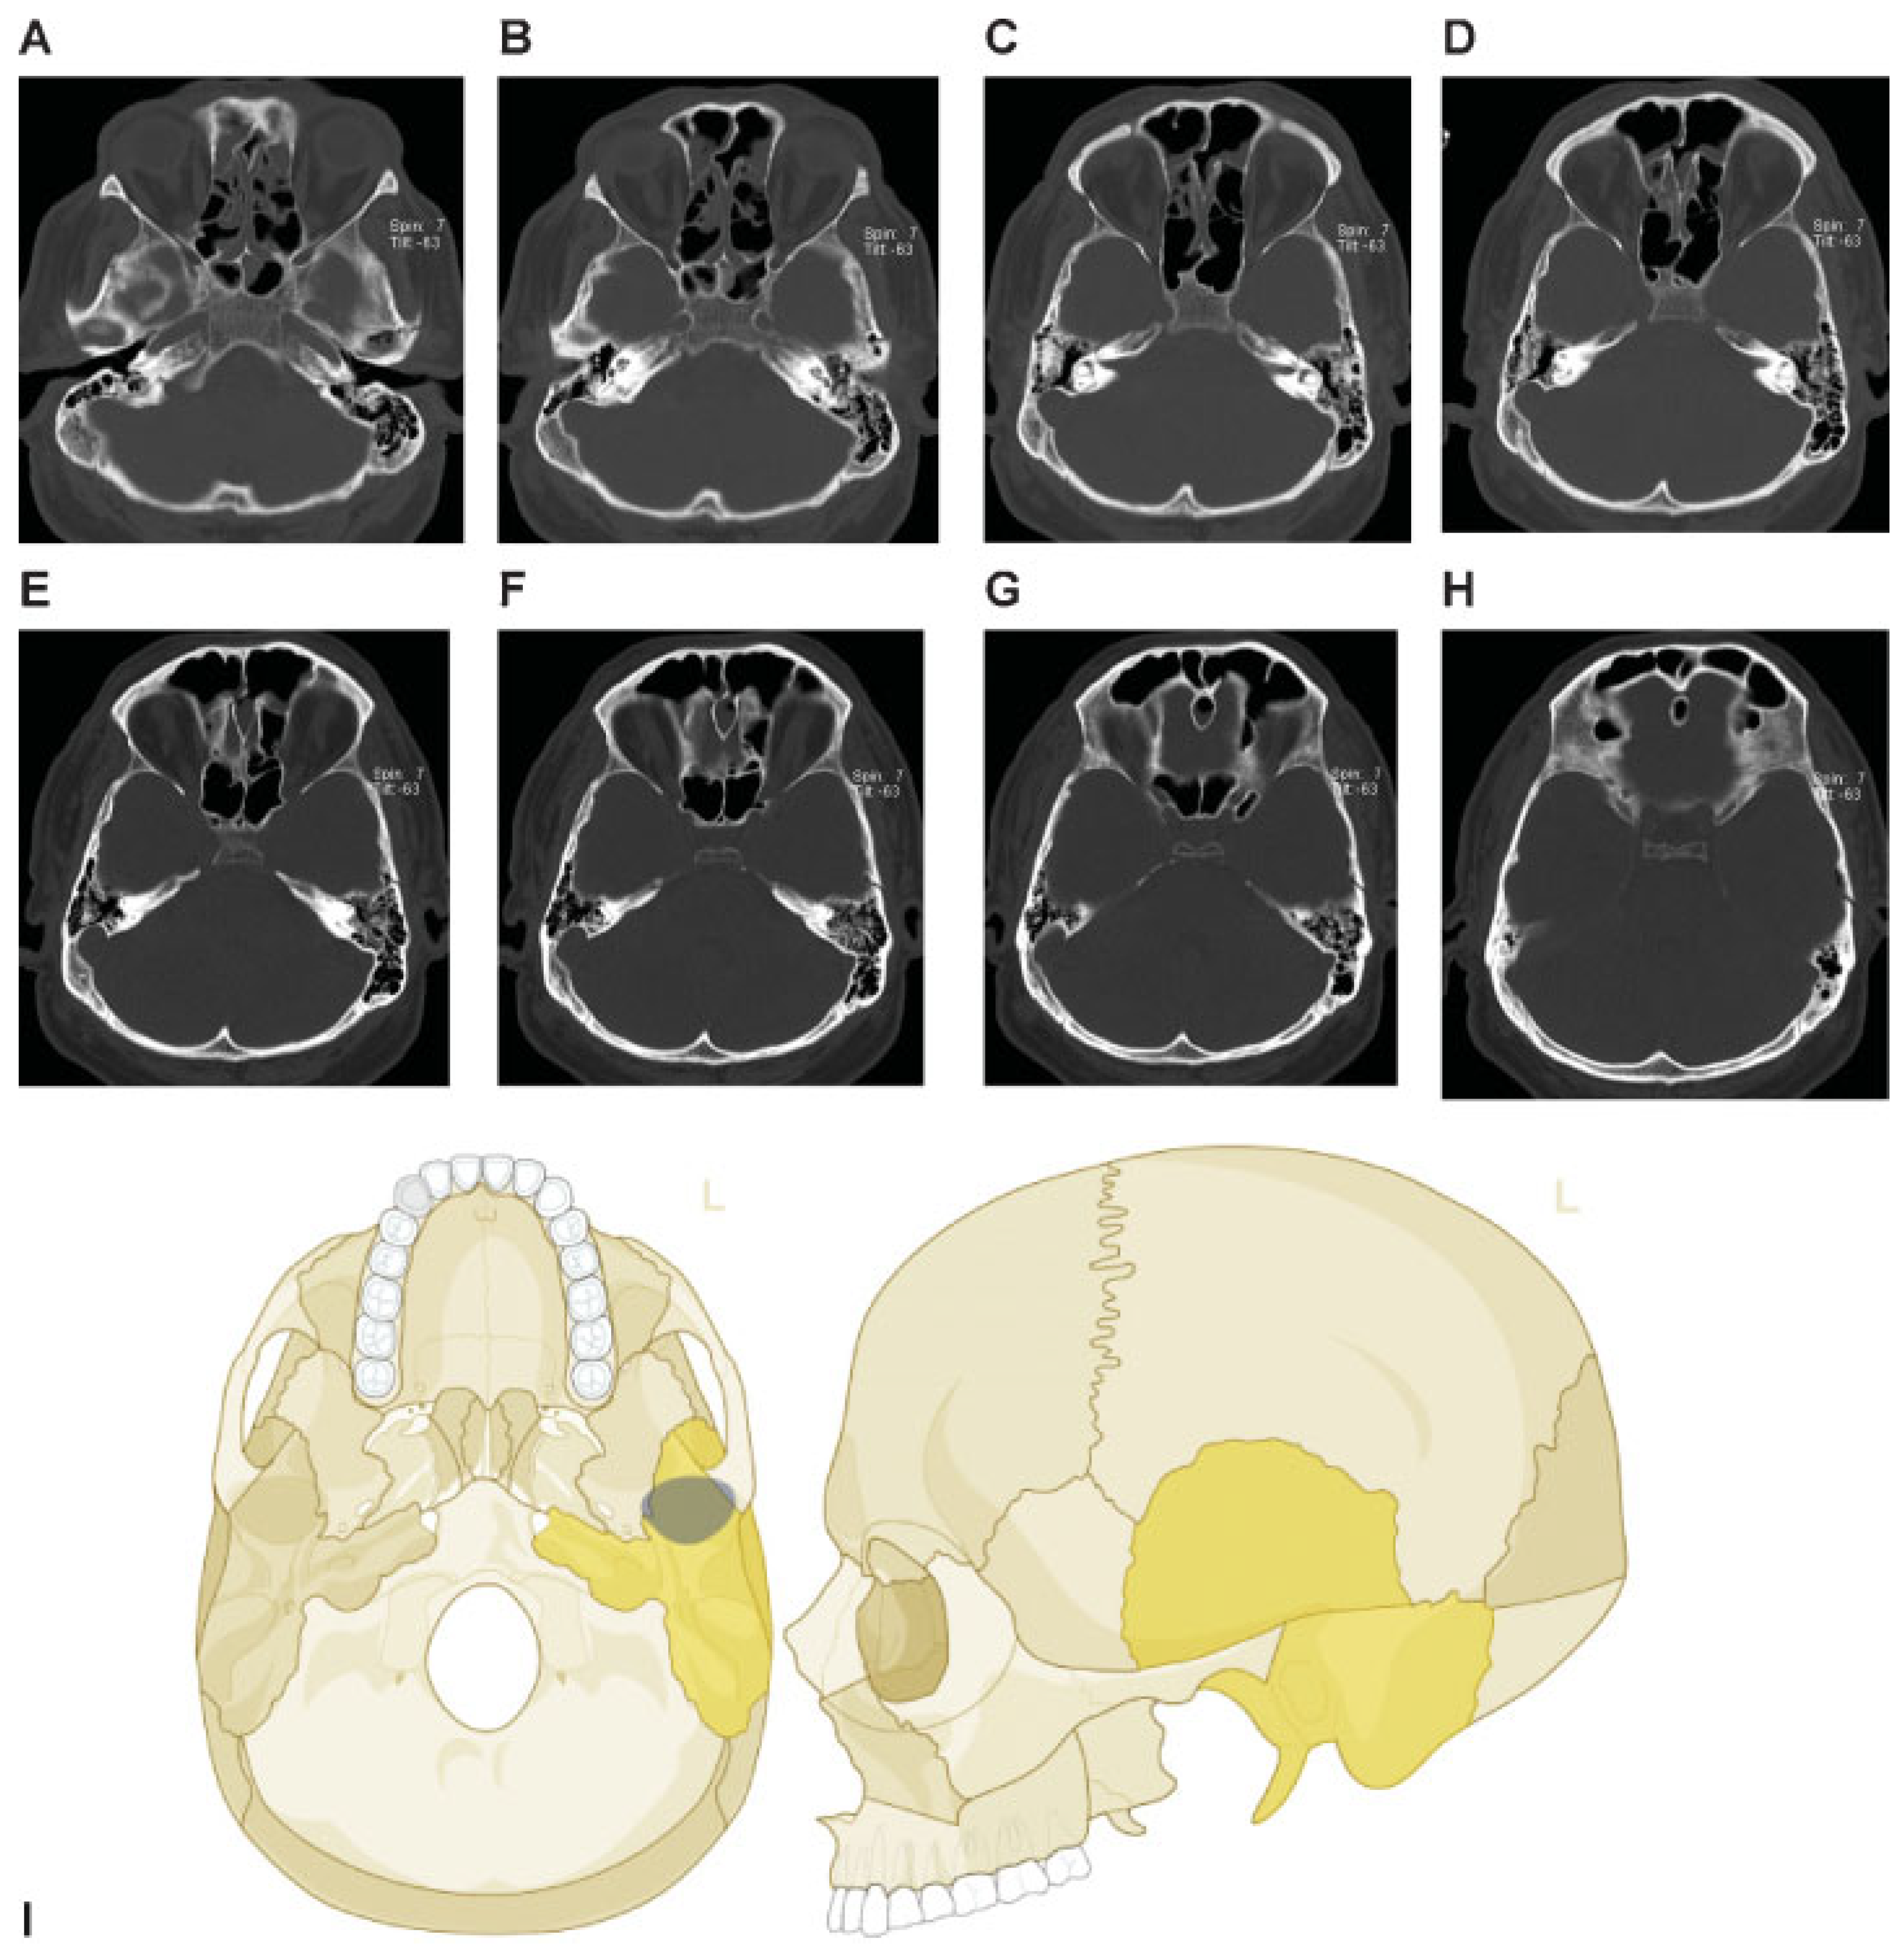

This coding system allows description of most relevant fracture patterns as illustrated in the case examples, such as the differentiation between unilateral or bilateral fracture patterns. In a series of three case examples, we illustrate the coding of a case with multiple cranial vault fractures (Figure 5), a single skull base fracture extending into the temporal cranial vault (Figure 6) and a right occipital and temporal cranial vault fracture extending into right middle fossa skull base (Figure 7). A range of additional fracture patterns are presented in a special case appendix as electronic supplement to this issue of the Journal (www.aocmf.org/classification).

Figure 7. Right occipital and temporal cranial vault fracture extending into the right middle fossa skull base. (A–C) Right occipital cranial vault fracture extending inferiorly into the right temporal bone, (D–H) with extension across the right middle fossa skull base through the skull base portion of the right temporal bone. There does not appear to be any fragmentation. (D) A probable left sphenoid fracture may be noted as well. Imaging: Computed tomographic axial views. (I) Level 3 code: 93 T0.M0.m.S, 94 O0.m, This case example CMTR-93-94-003 is made available electronically for viewing using the AOCOIAC software at www.aocmf.org/classification.